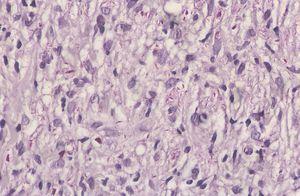

Se realizó biopsia de las lesiones cutáneas (figs. 2 y 3).

Fig. 3.—Estudio histológico: detalle del infiltrado histiocitario con infiltración neural (hematoxilina-eosina, ×40).

El estudio anatomopatológico mostró la presencia de un denso infiltrado de histiocitos vacuolados desde dermis profunda hasta dermis superficial con una banda subepidérmica respetada, compromiso neural del infiltrado y atrofia epidérmica (figs. 2 y 3). La tinción para bacilos ácido-alcohol resistentes fue claramente positiva (fig. 4).